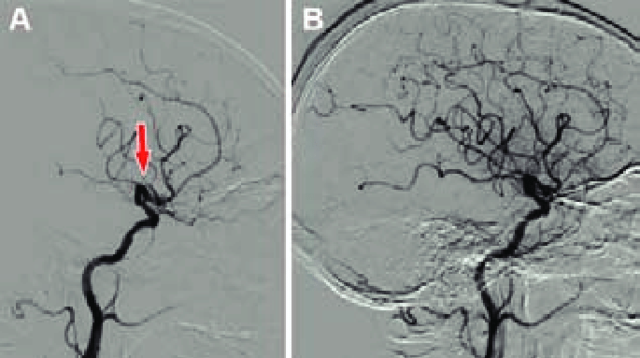

El Neurólogo Egas Moniz desarrollo la angiografía por contraste radiopaco para diagnosticar distintos trastornos cerebrales, desde tumores hasta malformaciones vasculares. El Neurólogo Egas Moniz desarrollo la angiografía por contraste radiopaco para diagnosticar distintos trastornos cerebrales, desde tumores hasta malformaciones vasculares.

Se desarrollo por primera vez el uso de la angiografía con ioduro de sodio en un joven de 20 años que tenia un tumor hipofisiario y un síndrome de BabinskyFrohlich. Se desarrollo por primera vez el uso de la angiografía con ioduro de sodio en un joven de 20 años que tenia un tumor hipofisiario y un síndrome de BabinskyFrohlich.

Fue el primero en utilizar ampliamente la arteriografía en muchas enfermedades medicas y quirúrgicas. Fue el primero en utilizar ampliamente la arteriografía en muchas enfermedades medicas y quirúrgicas.